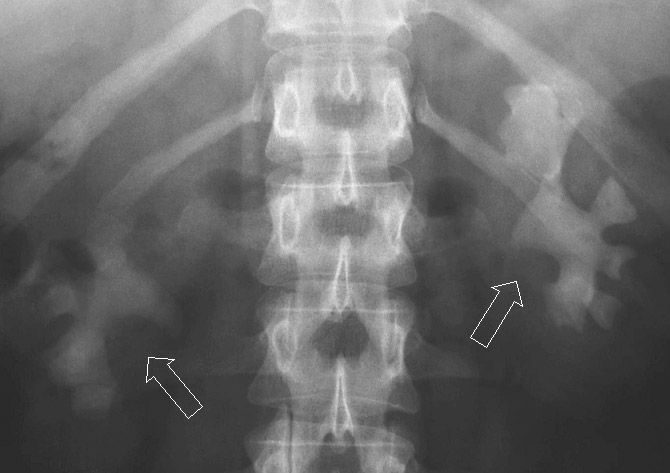

Röntgenaufnahme. Extreme Steinbildung in beiden Nieren. Beide Nierenhohlräume wurden innerhalb eines Jahres nahezu vollständig von Steinmaterial ausgefüllt ("Ausgußsteine"). (c) Urologische Klinik der Uniklinik Bonn